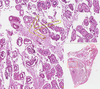

Testicular Atrophy Flashcards

Testicular Atrophy

Expanded Interstitium

Fibrous Envelope

Hyalinised Tubule —- Leydig Cells

Leydig Cells

Proliferated Leydig Cells

Sertoli Cells

Tubule with Spermatogonia and Primary Spermatocytes

Tubules with Germinative Epithelium

Tubules with thicker basement membranes